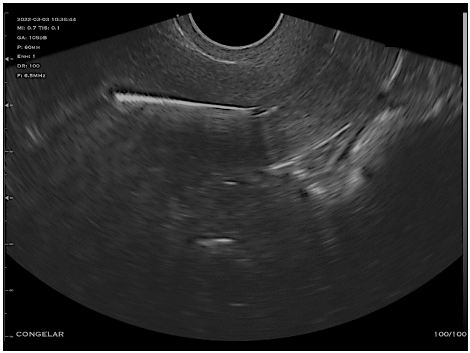

Paciente, 32 anos, DUM há quinze dias, em uso de DIU não hormonal há dois anos, comparece para realização de ultrassonografia para avaliação de posicionamento de DIU. Ao exame, é observada a imagem a seguir:

Qual a conclusão do exame?